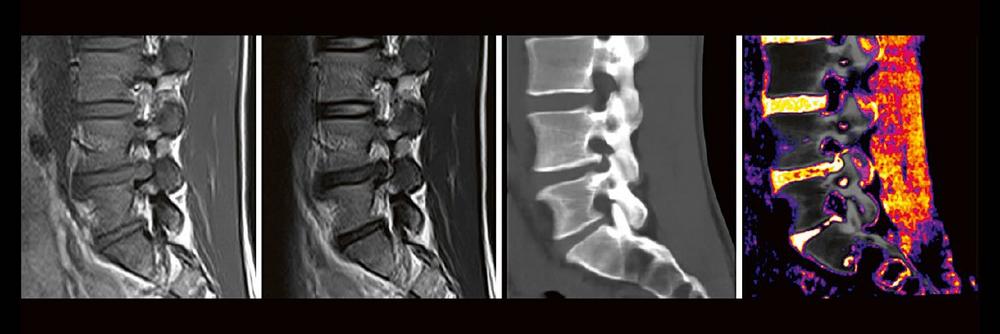

Dual-Energy CT der Wirbelsäule: Technik und klinische Praxis (Webinar | Online)

Professor Dr. med. Matthias PumbergerPD Dr. med. Torsten Diekhoff Die Dual-Energy-Computertomographie (DECT) hat für viele klinische Anwendungen bereits Einzug in die Praxis genommen. Für die […]